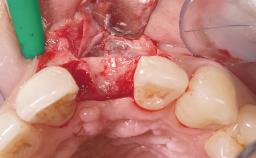

Late Flapless Placement of an Implant in a Maxillary Left Central Incisor Site

A 39-year-old male patient presented with a chief complaint of discomfort and gingival discoloration around his maxillary left central incisor. He was in good general health and was a non-smoker. His past dental history was significant because of the traumatic fracture of tooth 21 in a sporting accident at age 13. Initial dental treatment included endodontic therapy and a full-coverage restoration. The patient became symptomatic 5 years later, when structural failure of the tooth resulted in the dislodgment of the crown. Endodontic retreatment, apical surgery, and post-and-core restoration were performed.

Bone Augmentation Horizontal|Staged

Augmentation Materials Xenogenous|Membrane

Soft Tissue Grafting Simultaneous